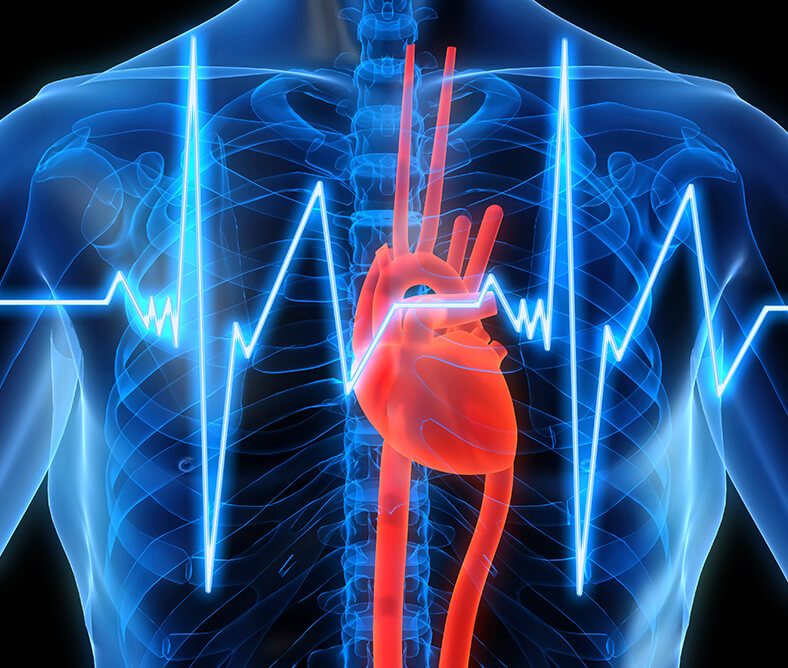

Ο καρδιακός μυς, όπως και κάθε άλλος ιστός στο ανθρώπινο σώμα, χρειάζεται οξυγόνο για να ζήσει. Το έμφραγμα προκύπτει όταν η ροή του αίματος, η οποία και τροφοδοτεί την καρδιά με το απαραίτητο οξυγόνο, μειωθεί σοβαρά ή διακοπεί πλήρως.

Υπάρχει θεραπεία; O Επεμβατικός Καρδιολόγος Αθανάσιος Πατιαλιάκας μας μίλησε για τους τρόπους αντιμετώπισης δείτε το απόσπασμα από την εκπομπή "Στο Κόκκινο".